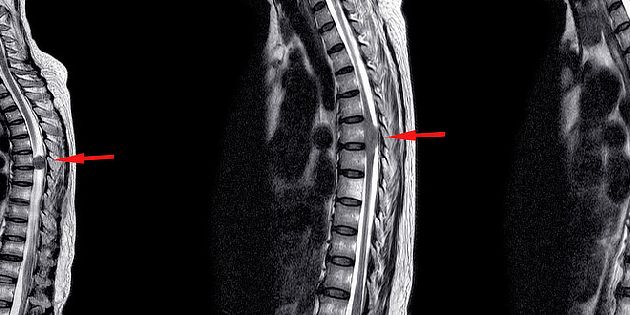

Nádory míchy

Nádory míchy se vyskytují poměrně zřídka a ve většině případů jsou nezhoubné. Jakmile však dosáhn...